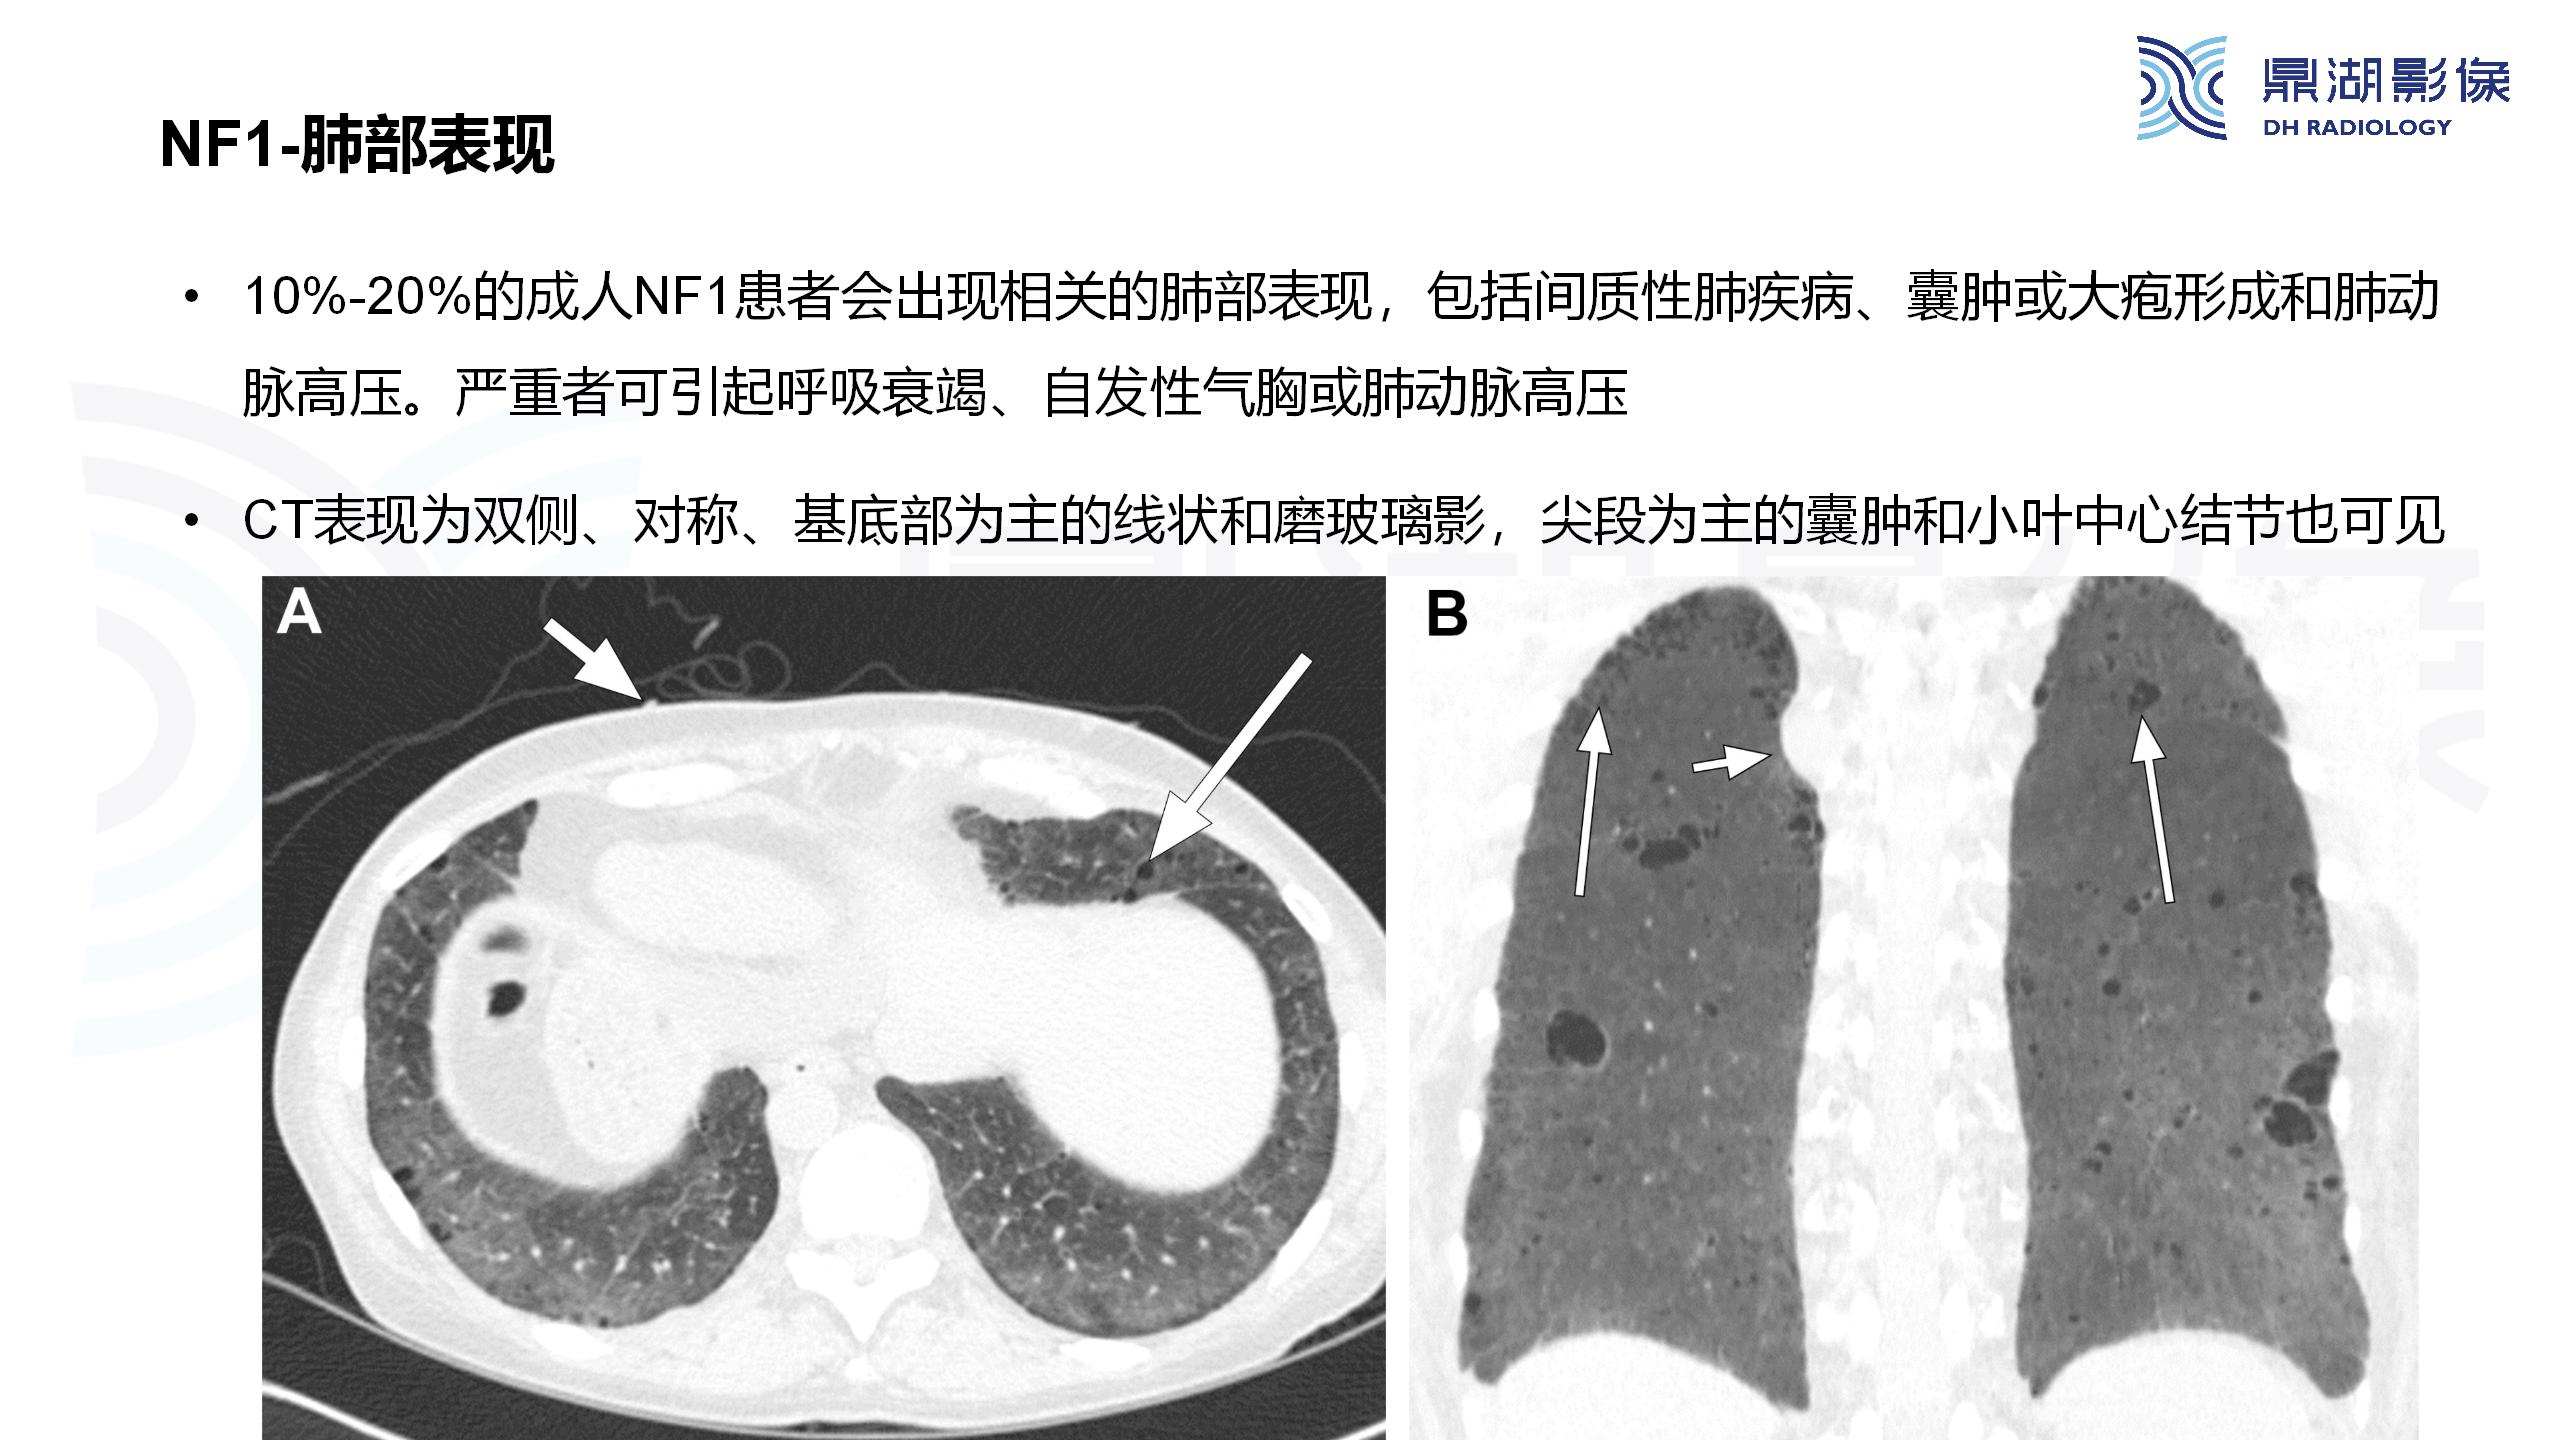

神经纤维瘤病(NF1)